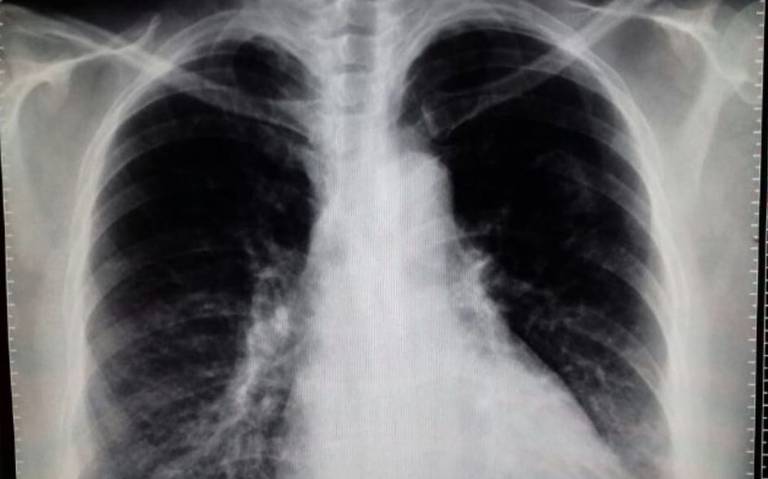

Asociación entre antidepresivos con neumonía y exacerbación en pacientes con EPOC: una serie de casos autocontrolados

26 junio 2023

Los antidepresivos se asociaron con un mayor riesgo tanto de neumonía como de exacerbación en pacientes con EPOC, disminuyendo los riesgos al suspender el tratamiento. Estos hallazgos sugieren una estrecha vigilancia de los efectos secundarios de la prescripción de antidepresivos y la consideración de intervenciones no farmacológicas. Thorax, 19 de junio de 2023